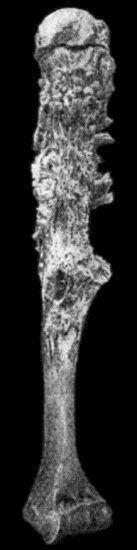

| 19. | Tibia and Fibula, showing changes due to Chronic Ulcer of Leg | 80 |

| 125. | Tuberculous Disease of Tibia | 457 |